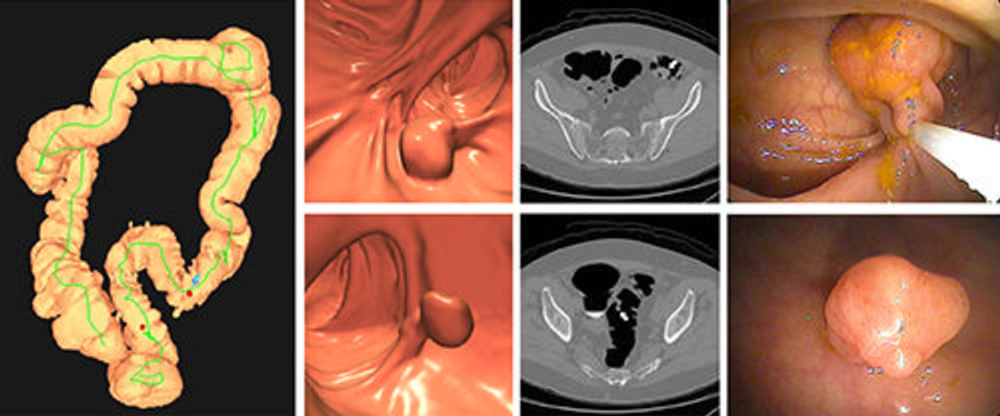

Figure 2. Images of positive CT colonography (CTC) screening examination result in an asymptomatic 67-year-old man. Three-dimensional colon map from CTC (left image) shows the location of two sigmoid polyps that were detected (red dots). Three-dimensional endoluminal and confirmatory two-dimensional transverse CTC images show a large 1.6- cm pedunculated polyp on top row (arrow) and a 9-mm pedunculated polyp in the distal sigmoid on the bottom row (arrow). Both polyps were confirmed and resected at optical colonoscopy performed the same day (right images), avoiding the need for a second bowel preparation. The larger polyp proved to be a tubulovillous adenoma (large advanced adenoma), whereas the smaller polyp was a nonadvanced tubular adenoma. Compare this level of information of a positive CTC screening test result with a positive multitarget stool DNA test result, for which no specific information is provided.